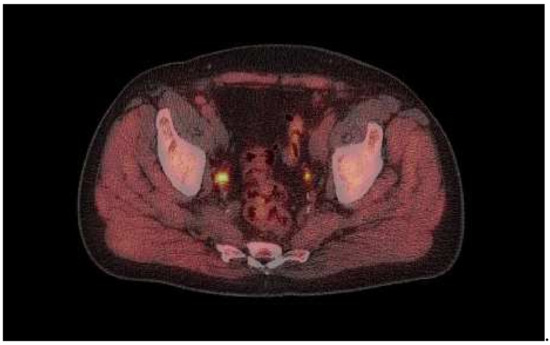

Of the 73 scans, 60 (82%) showed 18F-fluciclovine-positive lesions. In total, 33/73 (45%) of the scans showed localized uptake consistent with malignancy (“positive” findings) in the prostate or prostate bed, and 46/73 (63%) showed lesions outside of the prostate or prostate bed (example case provided in Figure 1). Extraprostatic disease included lymphatic spread in 38/73 (52%) and bone lesions in 5/73 (6.8%). No pulmonary or liver metastases were detected. Sclerotic bone lesions without increased tracer uptake were observed in two patients. One of these had no other 18F-fluiciclovine findings, while the other patient had increased uptake in pelvic lymph nodes, which was suspicious for malignancy.

Figure 1.

18F-fluciclovine PET example image.

Image captured from a 74-year-old male showing 18F-fluciclovine-avid lesion in right side iliaca interna lymph node (SUV 12).

The patient had undergone robotic-assisted laparoscopic prostatectomy in 2010 and salvage surgery in 2014, following a PSA rise to 12 ng/mL. Post-salvage surgery, his PSA was 0.3 ng/mL, but this slowly increased until bicalutamide was prescribed, initially intermittently, but continuously for the 9 months prior to the scan. PSA at the time of scanning was 4.9 ng/mL.